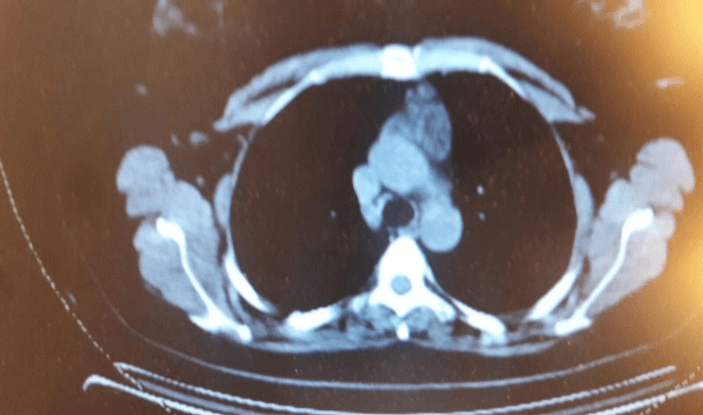

The patient is a 39-year-old gravida 3 P2102 woman who had undergone total abdominal hysterectomy with bilateral salpingo-oophorectomy for stage 1C2 (T1C2-N0-M0) according to FIGO and TNM staging systems endometrioid ovarian cancer in June of 2018. The tumor was ER(+), WT1(+), P16 and P53(-). In August of 2018, a 6 cycles of adjuvant chemotherapy with Adriamycin and cisplatin was begun, completed in February of 2019. Thereafter, the patient reached complete remission and was referred to follow-up. 8 months later a CT chest scan revealed a 6 cm mass in the anterior mediastinum. The patient meanwhile was in excellent condition, tumor markers were within normal limits and no other signs of relapse were evident. Consequently, the patient was referred to our department for consultation and further evaluation.

Figure 1: CT scan documents the anterior mediastinal mass.

Baseline CT scan (post adjuvant chemotherapy): 1.5 cm anterior mediastinal mass; CT scan: 6 cm anterior mediastinal mass (Figures 1 & 2); PET scan: Showed no uptake in the thymus; CBC with differential showed no abnormalities or atypical lymphocytosis prior or to and after the development of thymic mass; Physical examination: No clinical signs or symptoms of myasthenia Gravis.

Figure 2: CT scan shows the anterior mediastinal mass.